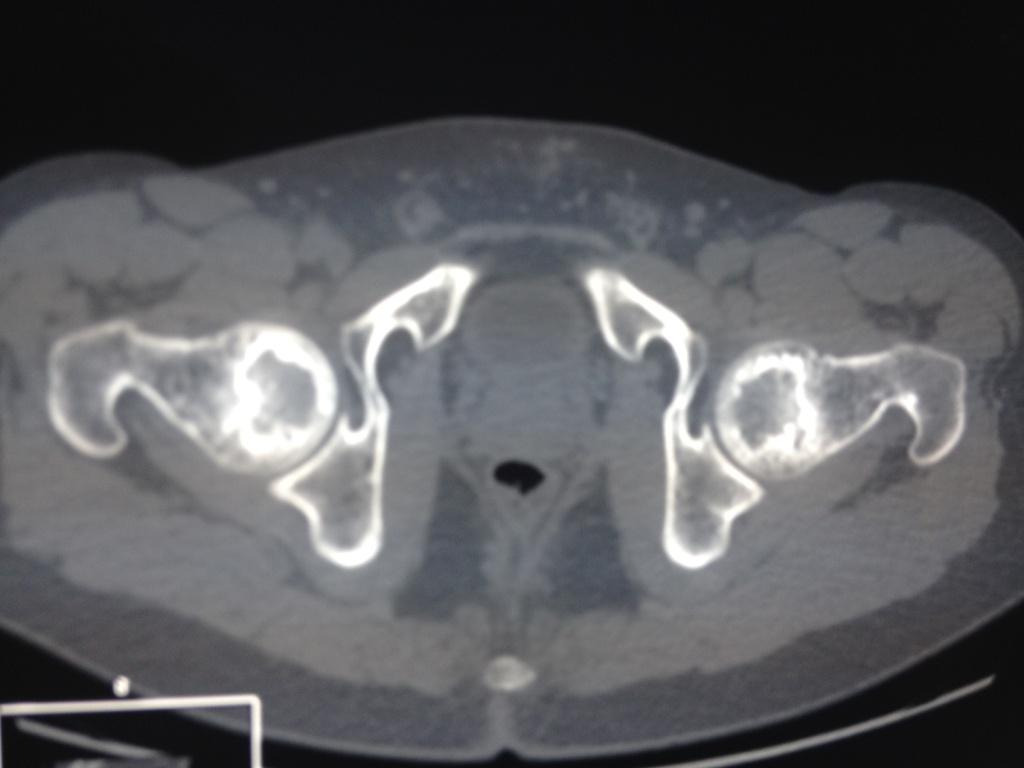

Пациента,32 лет.беспокоят боли в левом тазобедренном суставе. Болеет около 2 лет. Клинически - незначительные боли и ограничение ротации. Данные Рент, КТ, МРТ прилагаются